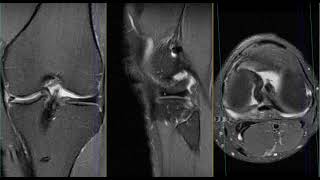

Menisco Interno Menisco Roto Resonancia, RM rotura en asa de cubo menisco interno., 16.48 MB, 12:00, 27,345, Dr Victor Cantarero, 2021-04-05T20:14:28.000000Z, 3, Resonancia de rodilla menisco roto | Actualizado septiembre 2022, larachacf.es, 558 x 933, jpeg, WebLa rotura de menisco se puede diagnosticar a través de una exploración fisica y una resonancia imantada. En casos puntuales de duda, el experta podrá decantarse por. WebResonancia magnética con rotura de menisco interno: podría ser candidato a cirugía. ¿Cómo se opera el menisco? Hoy en día, el 100% de las. , 20, menisco-interno-menisco-roto-resonancia, Novedades y Muebles WebLa rotura de menisco se puede diagnosticar a través de una exploración fisica y una resonancia imantada. En casos puntuales de duda, el experta podrá decantarse por. WebResonancia magnética con rotura de menisco interno: podría ser candidato a cirugía. ¿Cómo se opera el menisco? Hoy en día, el 100% de las.

WebLa rotura de menisco se puede diagnosticar mediante una exploración física y una resonancia magnética. En casos puntuales de duda, el especialista podrá optar. WebResonancia magnética para un menisco interno desgarrado Mucho más frecuente es el desgarro de menisco interno agudo/fresco. En este caso, la resonancia magnética (RM).

WebMenisco Roto | El mejor tratamiento conservador. Estas son las fases del tratamiento que hay que seguir para quitar el dolor del menisco roto. 1. Fisioterapia. Un buen trabajo de. WebCon la gran cantidad de tratamientos hoy en día para las lesiones de menisco, los cirujanos y fisioterapeutas necesitan conocer con detalle el estado del menisco interno o externo.. WebUn menisco roto será especialmente significativo si hay lesiones asociadas como la rotura de ligamento cruzado anterior o lesión en el cartílago articular (4). La. WebSignos en Resonancia magnética de la rotura en asa de cubo del menisco interno. WebEl bloqueo de rodilla por menisco roto se debe a que ese fragmento se coloca en medio de la articulación y evita el correcto funcionamiento de la rodilla.. WebUna rotura del menisco puede ser el resultado de cualquier actividad que haga que te tuerzas o gires la rodilla con fuerza, como pivotes agresivos o paradas y.